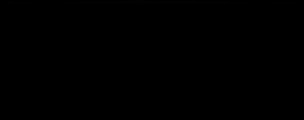

症例240代 女性 主訴 義歯が動いて煩わしい

治療前

治療後

入れ歯だと奥歯しっかり噛めず、取り外しも煩わしいので固定制のインプラントにして欲しいと訴え来院。

左右大臼歯部は、残存骨が1~2㎜程度で骨高が不足している為、ソケットリフト(上顎洞洞底膜挙上術)を行い、インプラントを埋入。口腔内全体で7本のインプラントを埋入。

約4ヶ月の治療期間を経て、全てジルコニアを装着し終了。

リスクとしては外科的侵襲がある。デメリットは、保険外診療の為、経済的負担がある。

費用 381万(税込)(オペ・仮歯・最終補綴物まで含む)